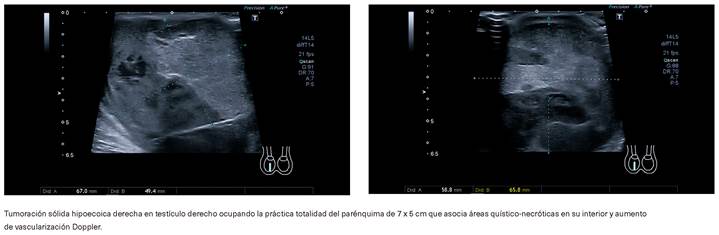

Ante la sintomatología del paciente y la presencia de datos de alarma (tumoración indolora con transiluminación negativa), se extrae analítica sanguínea en la que destacan proteína C reactiva (PCR) 90,8 mg/L [0-0,5], lactato deshidrogenasa (LDH) 1.286 U/L [219-439], leucocitos 9460 µl, con uroanálisis sin alteraciones patológicas. La ecografía testicular (figura 1) muestra una tumoración sólida heterogénea e hipoecoica en testículo derecho ocupando la práctica totalidad del parénquima de 7 x 5 cm asociando áreas quísticas y necróticas en su interior y aumento de vascularización Doppler.